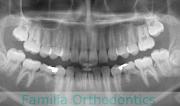

歯並びをきれいにしたいということで来院されました。非常に強い前歯の突出と叢生(でこぼこ)でした。上下左右から小臼歯を抜歯してマルチブラケット法にて治療を行いました。前歯の歯根が短く、歯根吸収のリスクが非常に高いケースでした。前歯に負担をかけないように3年弱、30回程度の通院で治療を行いました。